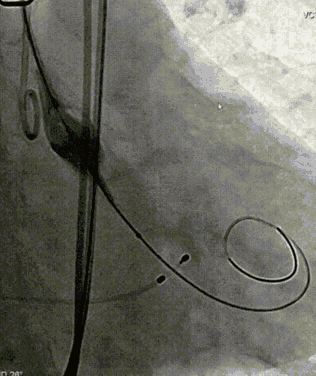

导丝跨瓣

球囊预扩

TaurusOne顺利过弓